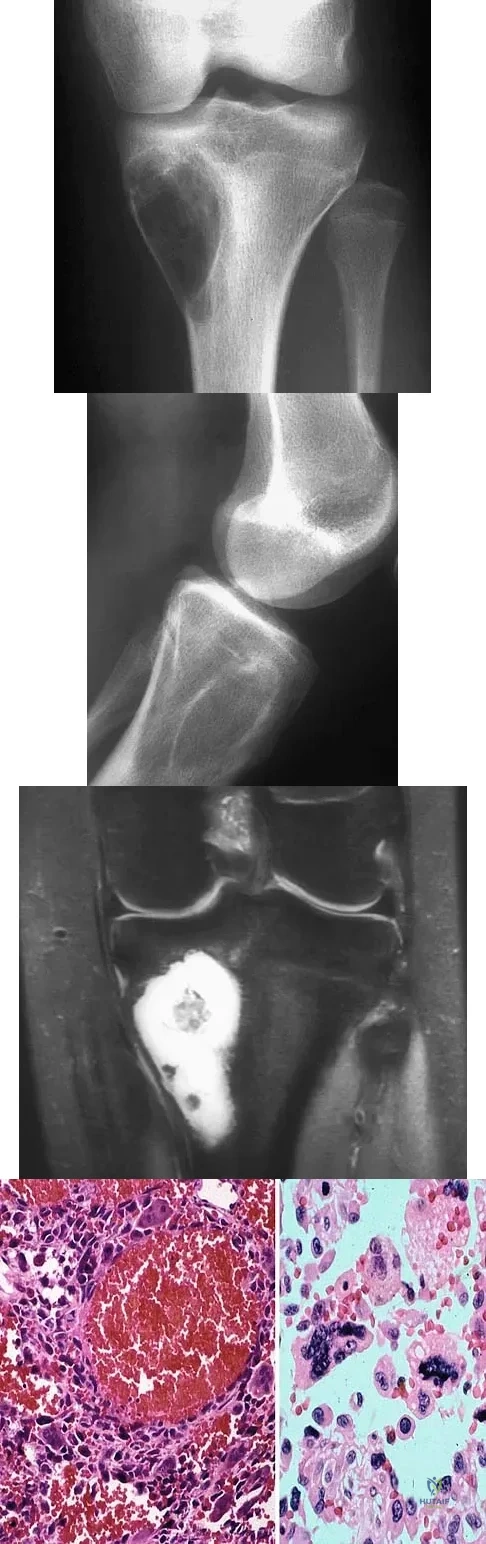

A 10-year-old child has leg discomfort with activity. A radiograph, bone scan, and biopsy specimen are shown in Figures 1a through 1c. What is the most likely diagnosis?

A 13-year-old boy has pain and a firm mass in his left knee. A radiograph and MRI scan are shown in Figures 2a and 2b, and a biopsy specimen is shown in Figure 2c. Based on these findings, what is the most likely diagnosis?

A 14-year-old patient has anterior knee pain. Radiographs, an MRI scan, and biopsy specimens are shown in Figures 6a through 6e. What is the most likely diagnosis?

A 12-year-old girl has had right knee pain for the past 3 months. Radiographs and a coronal T2-weighted MRI scan are shown in Figures 10a through 10c. A biopsy specimen is shown in Figure 10d. What is the most appropriate treatment for this lesion?